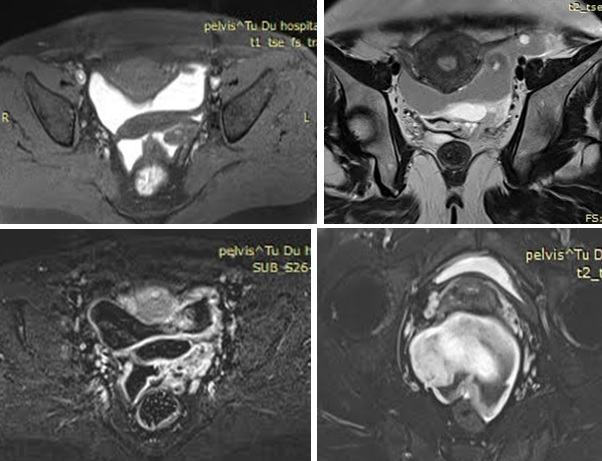

– Bệnh nhân được chụp MRI bụng chậu: Tử cung và hai buồng trứng bình thường. Cùng đồ sau và lan qua hai hố chậu có tổn thương chủ yếu chứa dịch dạng máu với nhiều giai đoạn khác nhau, bên trong không có mô đặc, bắt Gado ở thành, kích thước# 77x 59x 84 mm, tín hiệu trung gian trên T2W, cao trên T1W, cao mạnh trên T1fs, bờ len lỏi giữa các ngách ở vùng chậu.

– Chẩn đoán MRI: Khối tụ máu nhiều giai đoạn vùng cùng đồ lan ra hố chậu hai bên.

Hình MRI: Hình ảnh khối tổn thương dạng dịch máu nhiều giai đoạn, ở cùng đồ sau lan qua hai hố chậu, bờ len lõi giữa các ngách của vùng chậu, tín hiệu trung gian trên T2W, tín hiệu cao trên T1W và cao mạnh tên T1FS